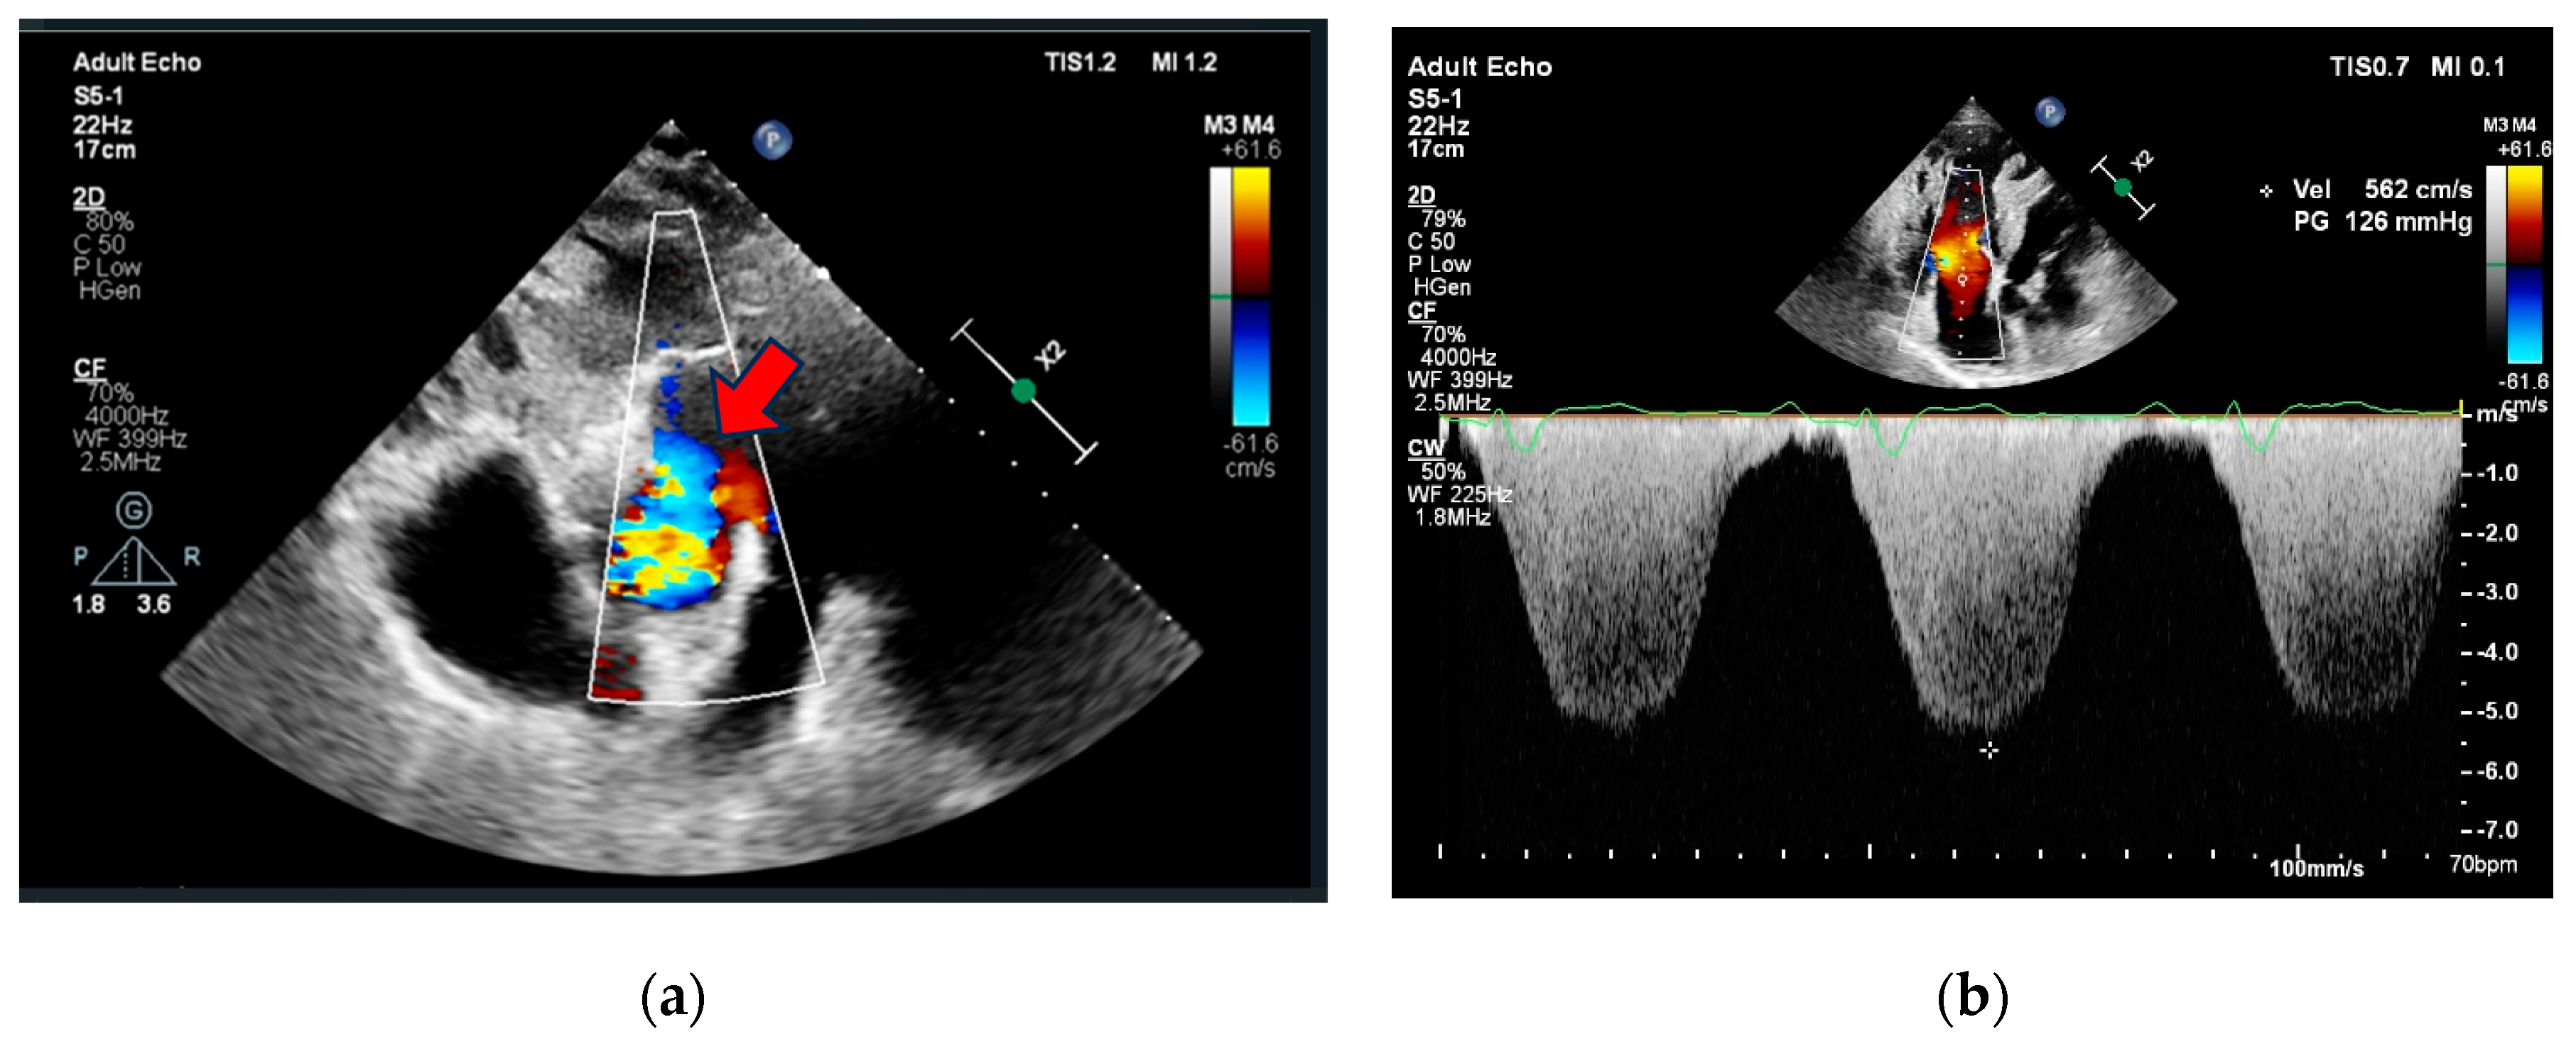

Initial investigations included an electrocardiogram (ECG), laboratory tests (biochemistry, D-dimer, Troponine I and B-Type Natriuretic Peptide levels), chest X-ray, and echocardiography. The case was discussed with pulmonologists at the PH center. Due to the deteriorating condition of the patient (increased dyspnea, elevated BNP levels, RV overload signs in ECG with no dynamic ST-segment and T-wave changes compared to previous ECG, reduced RV function, RV overload, and severe PH signs, preserved LV function without regional wall contraction abnormalities in echocardiography), a new PE episode could not be excluded. Initial clinical data are provided in Table 1 and Figure 1 and Figure 2. The patient was subsequently hospitalized in the pulmonology clinic for further investigation and treatment correction.

Figure 2. Echocardiography (a) parasternal short axis view showing aortopulmonic window (red arrow), (b) apical 4-chamber view showing right ventricle dilatation, hypertrophy, severe tricuspid regurgitation, and pulmonary hypertension.

2D TTELVEDD 46 mm (LVEDDi 24.08 mm/m2),

LV EF 50%. RV 48 mm, RA 50 mm, RV wall thickness 10 mm, S’ 6.5 cm/s, FAC 19.1%, moderate TR, PASP 133 mmHg, PA diameter 40 mm (Figure 2).